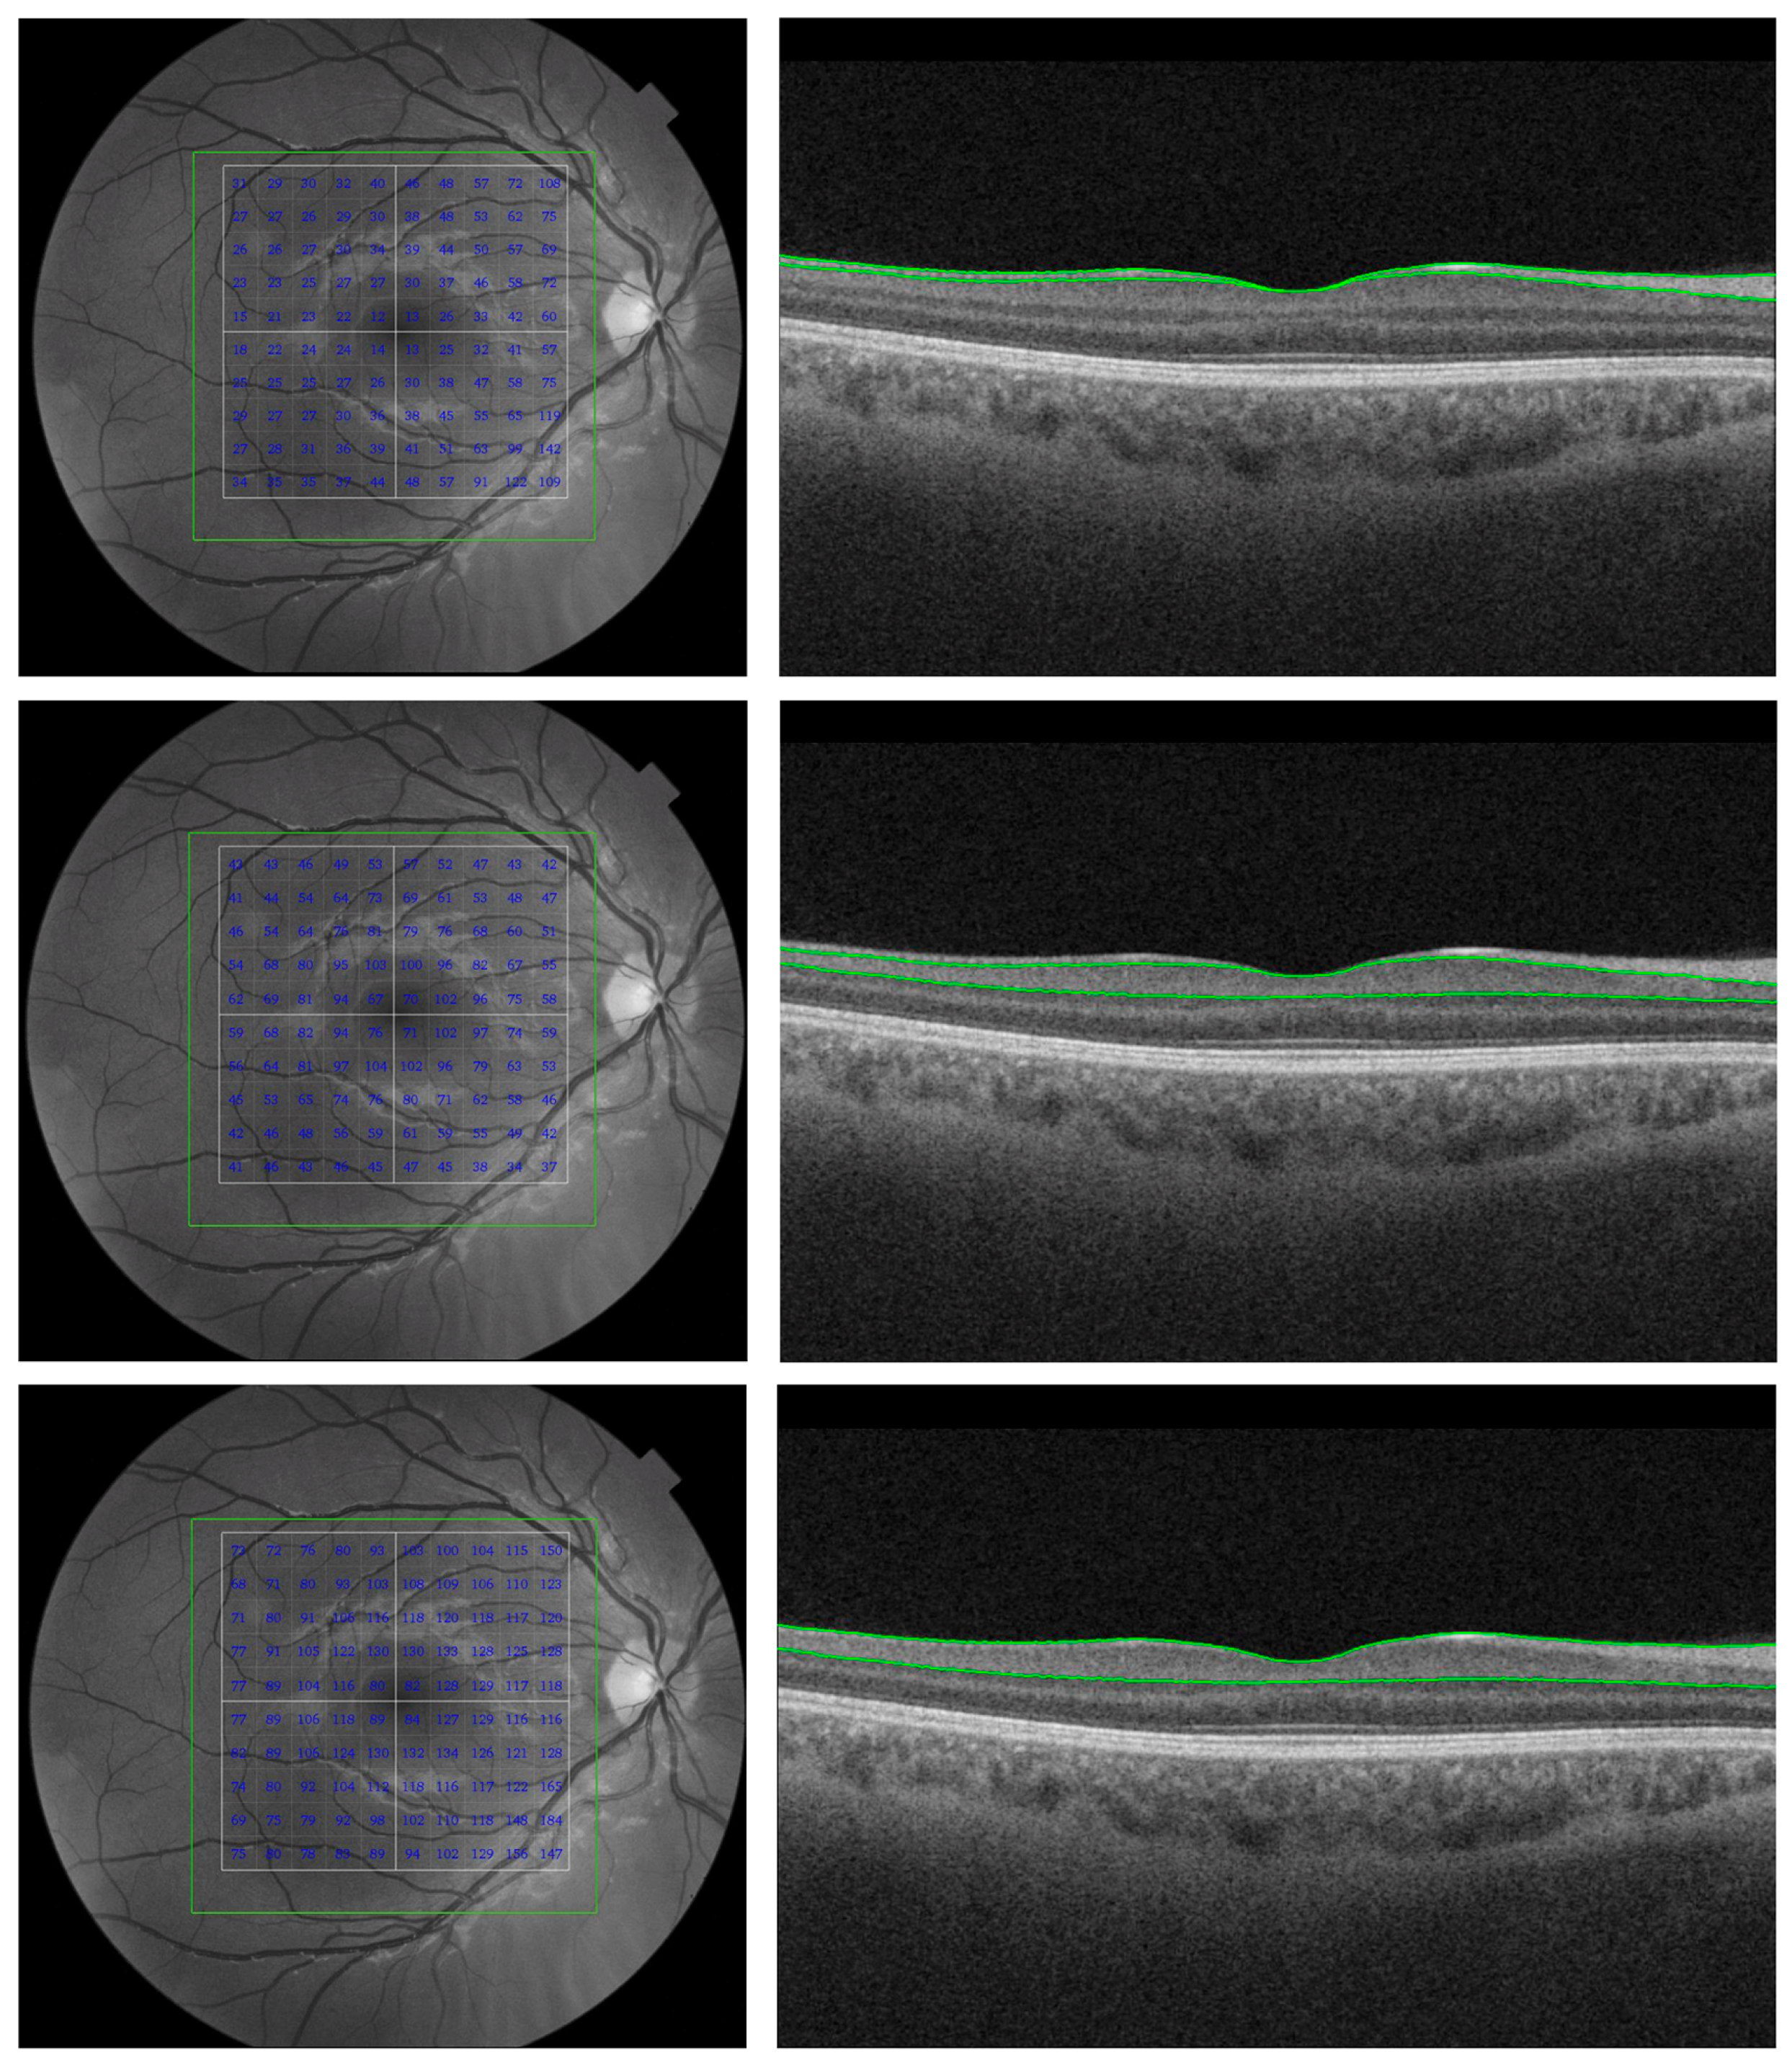

3.2. OCT Findings and Normative Data

3.3. OCT Findings Concerning Neuroimaging Features and Cognitive Tests

3.4. OCT Findings and AD Biomarkers

3.5. OCT Findings in Relation to Advanced Imaging and Electrophysiological Techniques